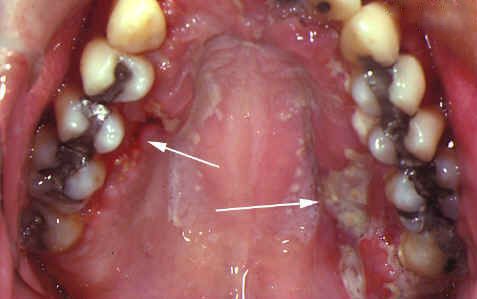

Aftowe zapalenie jamy ustnej (stomatitis aphthosa) to stan zapalny błony śluzowej jamy ustnej, który charakteryzuje się uszkodzeniem powierzchni nabłonka i pojawieniem się aft, czyli bolesnych erozji lub owrzodzeń. Zmiany te mogą występować pojedynczo lub w większej liczbie, mają okrągły lub owalny kształt i są pokryte białawo-żółtawym nalotem z czerwoną obwódką zapalną.

Kluczowym objawem aftowego zapalenia jamy ustnej jest pojawienie się pojedynczych lub mnogich aft, czyli bolesnych nadżerek (owrzodzeń) błony śluzowej jamy ustnej o średnicy 3–5 mm. Zmiany te mają najczęściej biały, żółtawy lub szarawy kolor i otoczone są czerwoną obwódką zapalną. Afty powodują znaczny dyskomfort — nawet delikatny kontakt z językiem, jedzeniem czy szczoteczką do zębów może wywoływać silny, kłujący ból, utrudniający mówienie i spożywanie posiłków.

Ostre aftowe zapalenie jamy ustnej charakteryzuje się nagłym wystąpieniem bolesnych owrzodzeń na błonie śluzowej jamy ustnej. Afty mają zwykle okrągły kształt, biały lub szarawy nalot i wyraźnie zaczerwienioną obwódkę. Błona śluzowa wokół nich jest obrzęknięta, tkliwa i bardzo wrażliwa na dotyk.

1. Postać włóknikowa (fibrynowa) – najczęstsza i najłagodniejsza forma choroby. Na błonie śluzowej jamy ustnej pojawiają się żółtawe plamy otoczone zaczerwienieniem. Na ich powierzchni tworzy się cienka warstwa włóknika, ściśle przylegająca do tkanek. W miarę rozwoju włóknik oddziela się, tworząc bolesne afty. Zwykle występuje 3–5 owrzodzeń, które goją się w ciągu 7–10 dni bez blizn.